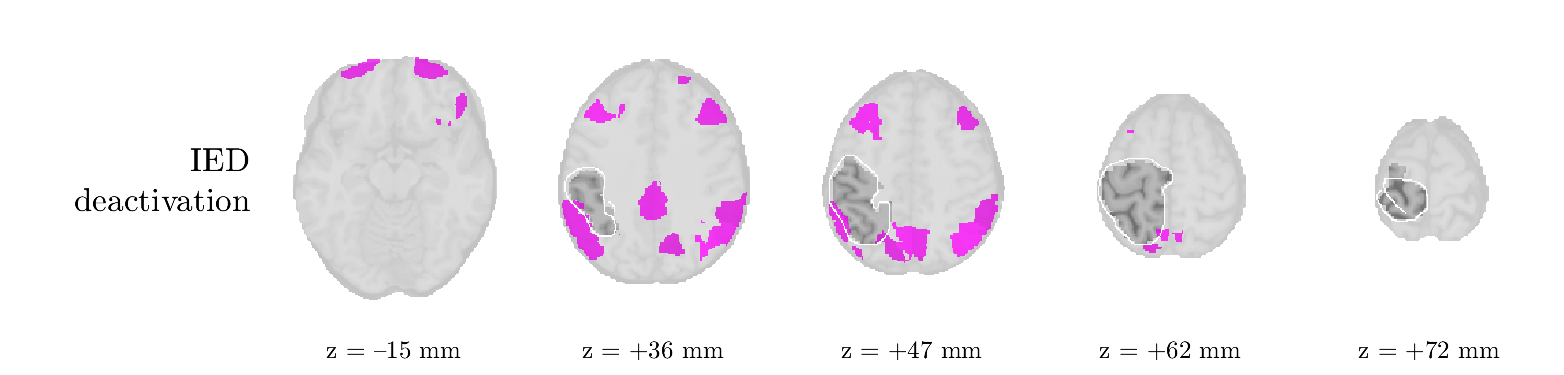

Patient 2

We analyze the solution with sources, and show the results in Figure 3 and 4. As for patient 1, we found a source which is strongly correlated to the MWF envelope, and which had a mostly low-frequency behavior characteristic for spikes. The topography is mostly uninformative, and does not clearly correspond to the patient’s clinical data. The third source is mostly present at both sides of the head, is very sparsely active in time, and has a high-frequency content: this is most likely an artifact due to the neck muscles. Again, there is one of the highest-entropy HRFs which belongs to a ROI in the IOZ. Now, the waveform is clearly resolved from the other HRFs, through the strong initial dip (before 0 seconds). Such a dip is sometimes observed in HRFs, but its underlying physiological mechanism is not yet fully understood. It is possible that this dip reflects altered vascular autoregulation near the IOZ (cfr. the explanation in the Section 1 of the main text), or a rapid depletion in oxygen due to IED generation (before the IED becomes visible on the EEG). Figure 4 furthermore shows that the IED-related component is significantly active in parts of the IOZ, and deactive in others. As mentioned earlier, this deactivation may or may not be due to errors in sign correction. Interestingly, the ROI with the high alteration in neurovascular coupling is distinct from both the activated and deactivated ROIs.